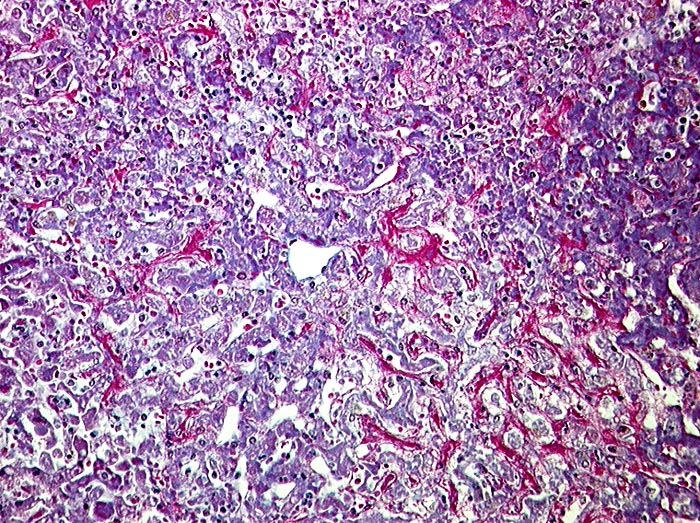

AP/ Subakute Stauung der Leber

Subakute Stauung der Leber

vaskulär / Durchblutungsstörung

Leber, Gallenwege, Pankreas

Leber

Morphologie

Pathologischer Befund